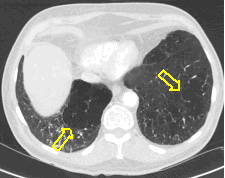

3b: Multiple lung metastasis, CT lung window (axial, coronal reformat)

Image

3c, coronal reformat

70 year old man, colon tumor.

Radiograph: Bilateral extensive, confluating patchy-nodular shadowing with diffuse reticular pattern. The diaphragm contour is partially blurry bilaterally: lymphangiosis carcinomatosa.

CT: Numerous 1-6 cm round and irregular, lobulated-spiculated contrast enhancing lesions in both lungs, everywhere sporadically.